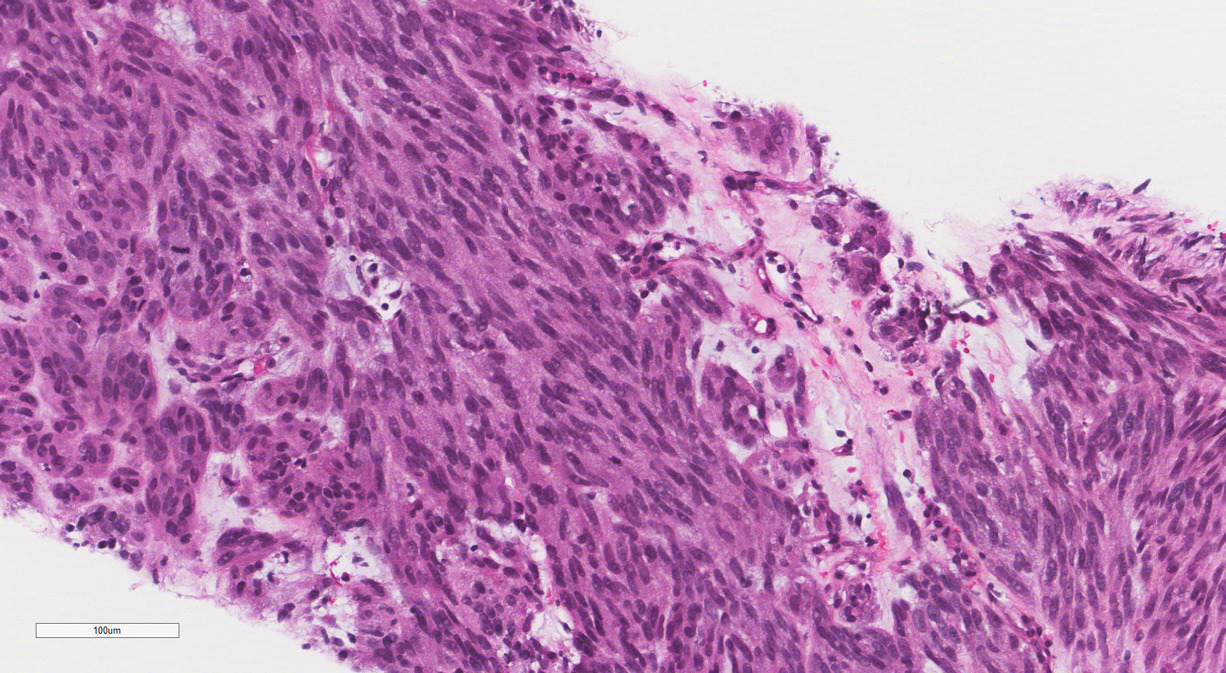

The patient was discharged home on postpartum day seven. At her surgical oncology appointment four weeks later, she continued to show signs of malnutrition with a weight loss of 20 kg compared to her intrapartum weight. An ultrasound-guided biopsy of her retroperitoneal mass confirmed the diagnosis of GIST with spindled morphology and multiple liver metastases (Figures 4 and 5). The patient’s case was reviewed in a multidisciplinary gastrointestinal tumor board, where neoadjuvant imatinib therapy was recommended. At her follow-up visit, the patient reported an increased appetite, and the size of her abdominal wall mass had decreased by approximately half. Due to an excellent initial response to imatinib therapy, this was to be continued with imaging at three-month intervals to assess her disease status; however, this plan was complicated by the SARS-CoV-2 pandemic, as the patient traveled oversees and was unable to return for several months. She did continue to take imatinib without difficulty during this time period.